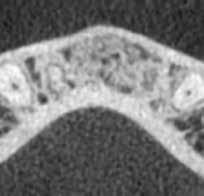

1. ábra: A 15-ös foggyökér meziális felszíne mellett látható radiolucens elváltozás, illetve a felvételen látható a korábban behelyezett gyökértömés, a parapulpális csap segítségével elhorgonyzott csonkfelépítés és a fogat borító cirkonkorona. –2. ábra: A saggitalis irányú CBCT-metszeten jól megfigyelhető az állcsontgerincet elérő radiolucens elváltozás. – 3. ábra: Az axiális irányú CBCT-metszeten egyértelműen látható a kezeletlen palatinális gyökércsatorna, valamint a radiolucens elváltozás mezio-disztális kiterjedése is jól megítélhető. – 4. ábra: A palatinális gyökércsatorna szelektív endodonciai kezelése során először gyógyszeres zárás került behelyezésre. – 5. ábra: A gyógyszeres zárás során alkalmazott kalcium-hidroxid alapú paszta a szulkuszon keresztül a szájüregbe extrudálódott. – 6. ábra: A gyökértömő anyag a középső és apikális gyökéri harmad határán lévő laterális csatornán keresztül a periapikális térbe extrudálódott. 7. ábra: A kezelések befejezését követően 4 évvel készült röntgenfelvételen jól látható a csontállomány gyógyulása és a fiziológiás gyökérhártyarés újbóli kialakulása. –8. ábra: A peroperatív CBCT-felvétel alapján készített koronális irányú metszeten jól látható a gyökércsúcs körül lévő periapikális felritkulás. – 9. ábra: A kezelések befejezése után 4 évvel készített CBCT-felvételen a gyulladásos lézió teljes megszűnése észlelhető.

A CBCT-készülékek endodonciai alkalmazásának talán az az egyik legnagyobb előnye, hogy így olyan anatómiai struktúrák is láthatóvá válnak, amelyeket egyébként nem tudnánk detektálni panoráma, cephalo, vagy periapicalis felvételek segítségével. Mivel a CBCT-felvételek kiértékelése számítógép segítségével történik, így a felvételek vizsgálata során lehetőségünk van az adott területet több nézőpontból és több síkban is megvizsgálni. 2015 októberében egy korábban a rendelőnkben kezelt 55 éves férfi páciens azzal a céllal kereste fel ismét a rendelőnket, hogy másodvéleményt kérjen egy jobb felső kvadránsban található fogával kapcsolatban. Egy másik rendelőben történő vizsgálat során a panaszos fog törését vélelmezték és a fog eltávolítását javasolták, illetve arról is beszámolt, hogy az elmúlt hét során ezen a területen egy puha duzzanat is kialakult. A klinikai vizsgálat során a jobb felső első és második kisőrlő között (14–15) egy fluktuáló duzzanatot észleltünk az áthajlásban. Az 15-ös fog mesialis oldalán 12 mm mély tasakot szondáztunk. A páciens által hozott periapicalis felvételen a 15-ös fog gyökércsúcsának mesialis részén egy nagy kiterjedésű radiolucens elváltozás volt észlelhető (1. ábra). A saggitális síkban vizsgált CBCT-felvételen (Carestream CS 9000, Carestream Dental) a lézió valódi kiterjedése is láthatóvá vált (2. ábra). A megelőző endodonciai kezelések során csupán a bukkális csatorna került detektálásra és gyökértöméssel való ellátásra. Az axiális irányú CBCT-szeleteken egyértelműen látható volt az ellátatlan palatinális gyökércsatorna (3. ábra)